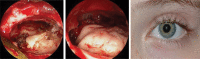

Management of frontal sinus fractures is controversial with no universally accepted treatment protocol. Goals of management are to correct aesthetic deformity, preserve sinus function when it is deemed salvageable, prevent sequela related to the injury, and minimize complications associated with intervention. Studies suggest that frontal sinus injuries, including disruption of the nasofrontal outflow tract (NFOT), can be managed nonoperatively in many cases. Advances in the utilization of endoscopic techniques have led to an evolution in management that reduces the need for open procedures, which have increased morbidity compared with endoscopic approaches. We employ a minimally disruptive protocol that treats the majority of fractures nonoperatively with serial clinical and radiographic examinations to assess for sinus aeration. Surgical intervention is reserved for the most severely displaced and comminuted posterior table fractures and unsalvageable NFOTs utilizing endoscopic approaches whenever possible.